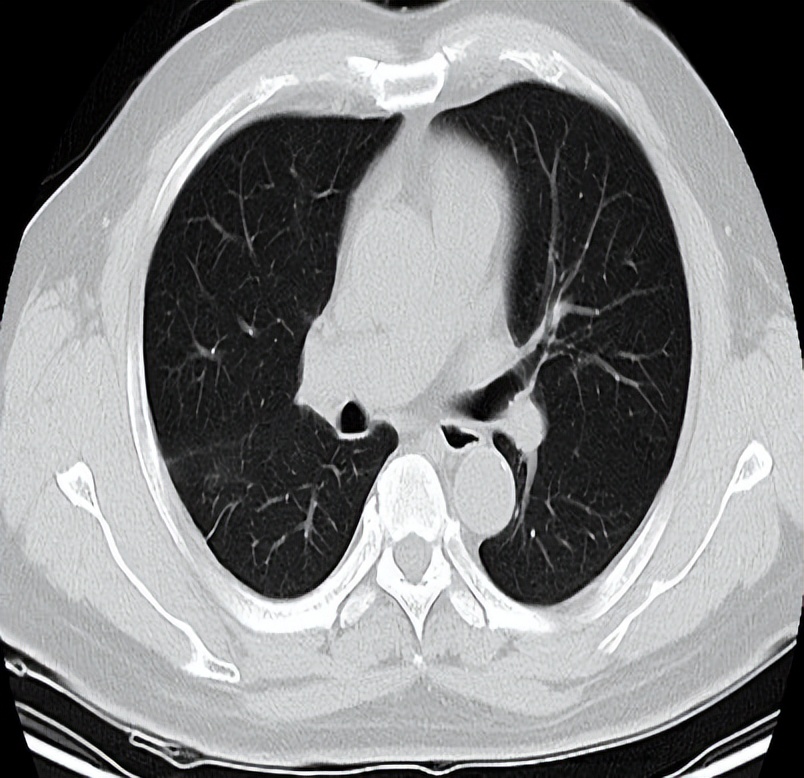

2022-3-6入院复查胸部CT见右肺上叶病灶增大,评价为病情进(PD),予以行胸部SBRT治疗,总剂量40Gy/8Fx。

放疗结束后予以培美曲赛+替雷利珠单抗治疗(培美曲塞0.9g d1+替雷利珠单抗200mg)治疗,现维持治疗至今(2022-8-20)。